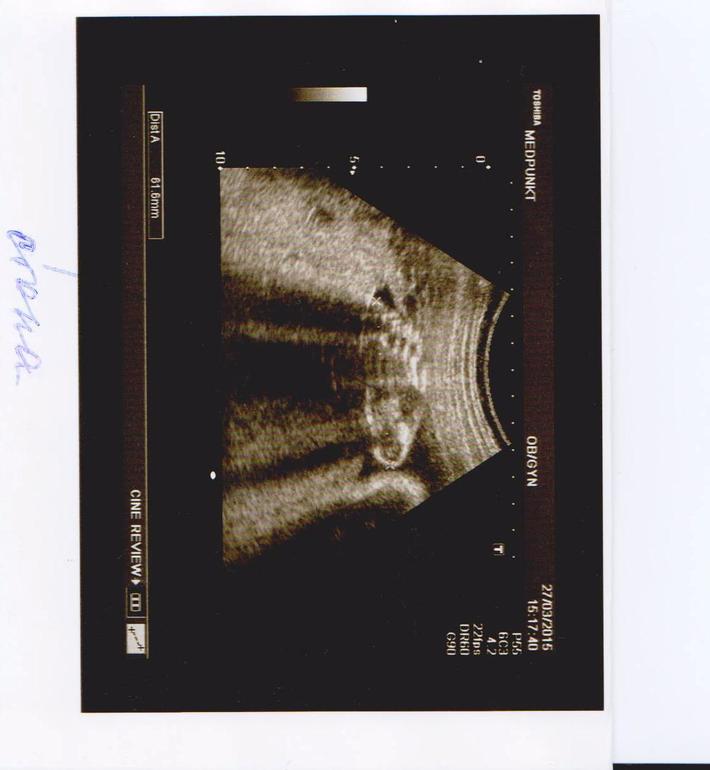

6 января ходили с мужем на узи, все показатели отличные, но вместо того что бы показать маме и папе свое "интересное место" малыш показал нам попу!

Но это ничего, главное здоровенький! А разглядеть еще 100 раз успеем.